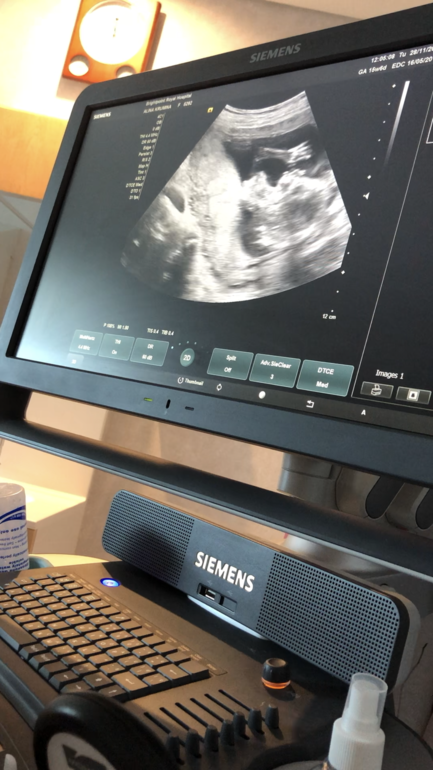

Вот мы передаём всем привет 💕💕💕💕

А тут демонстрируем кто мы 💕💕💕💕